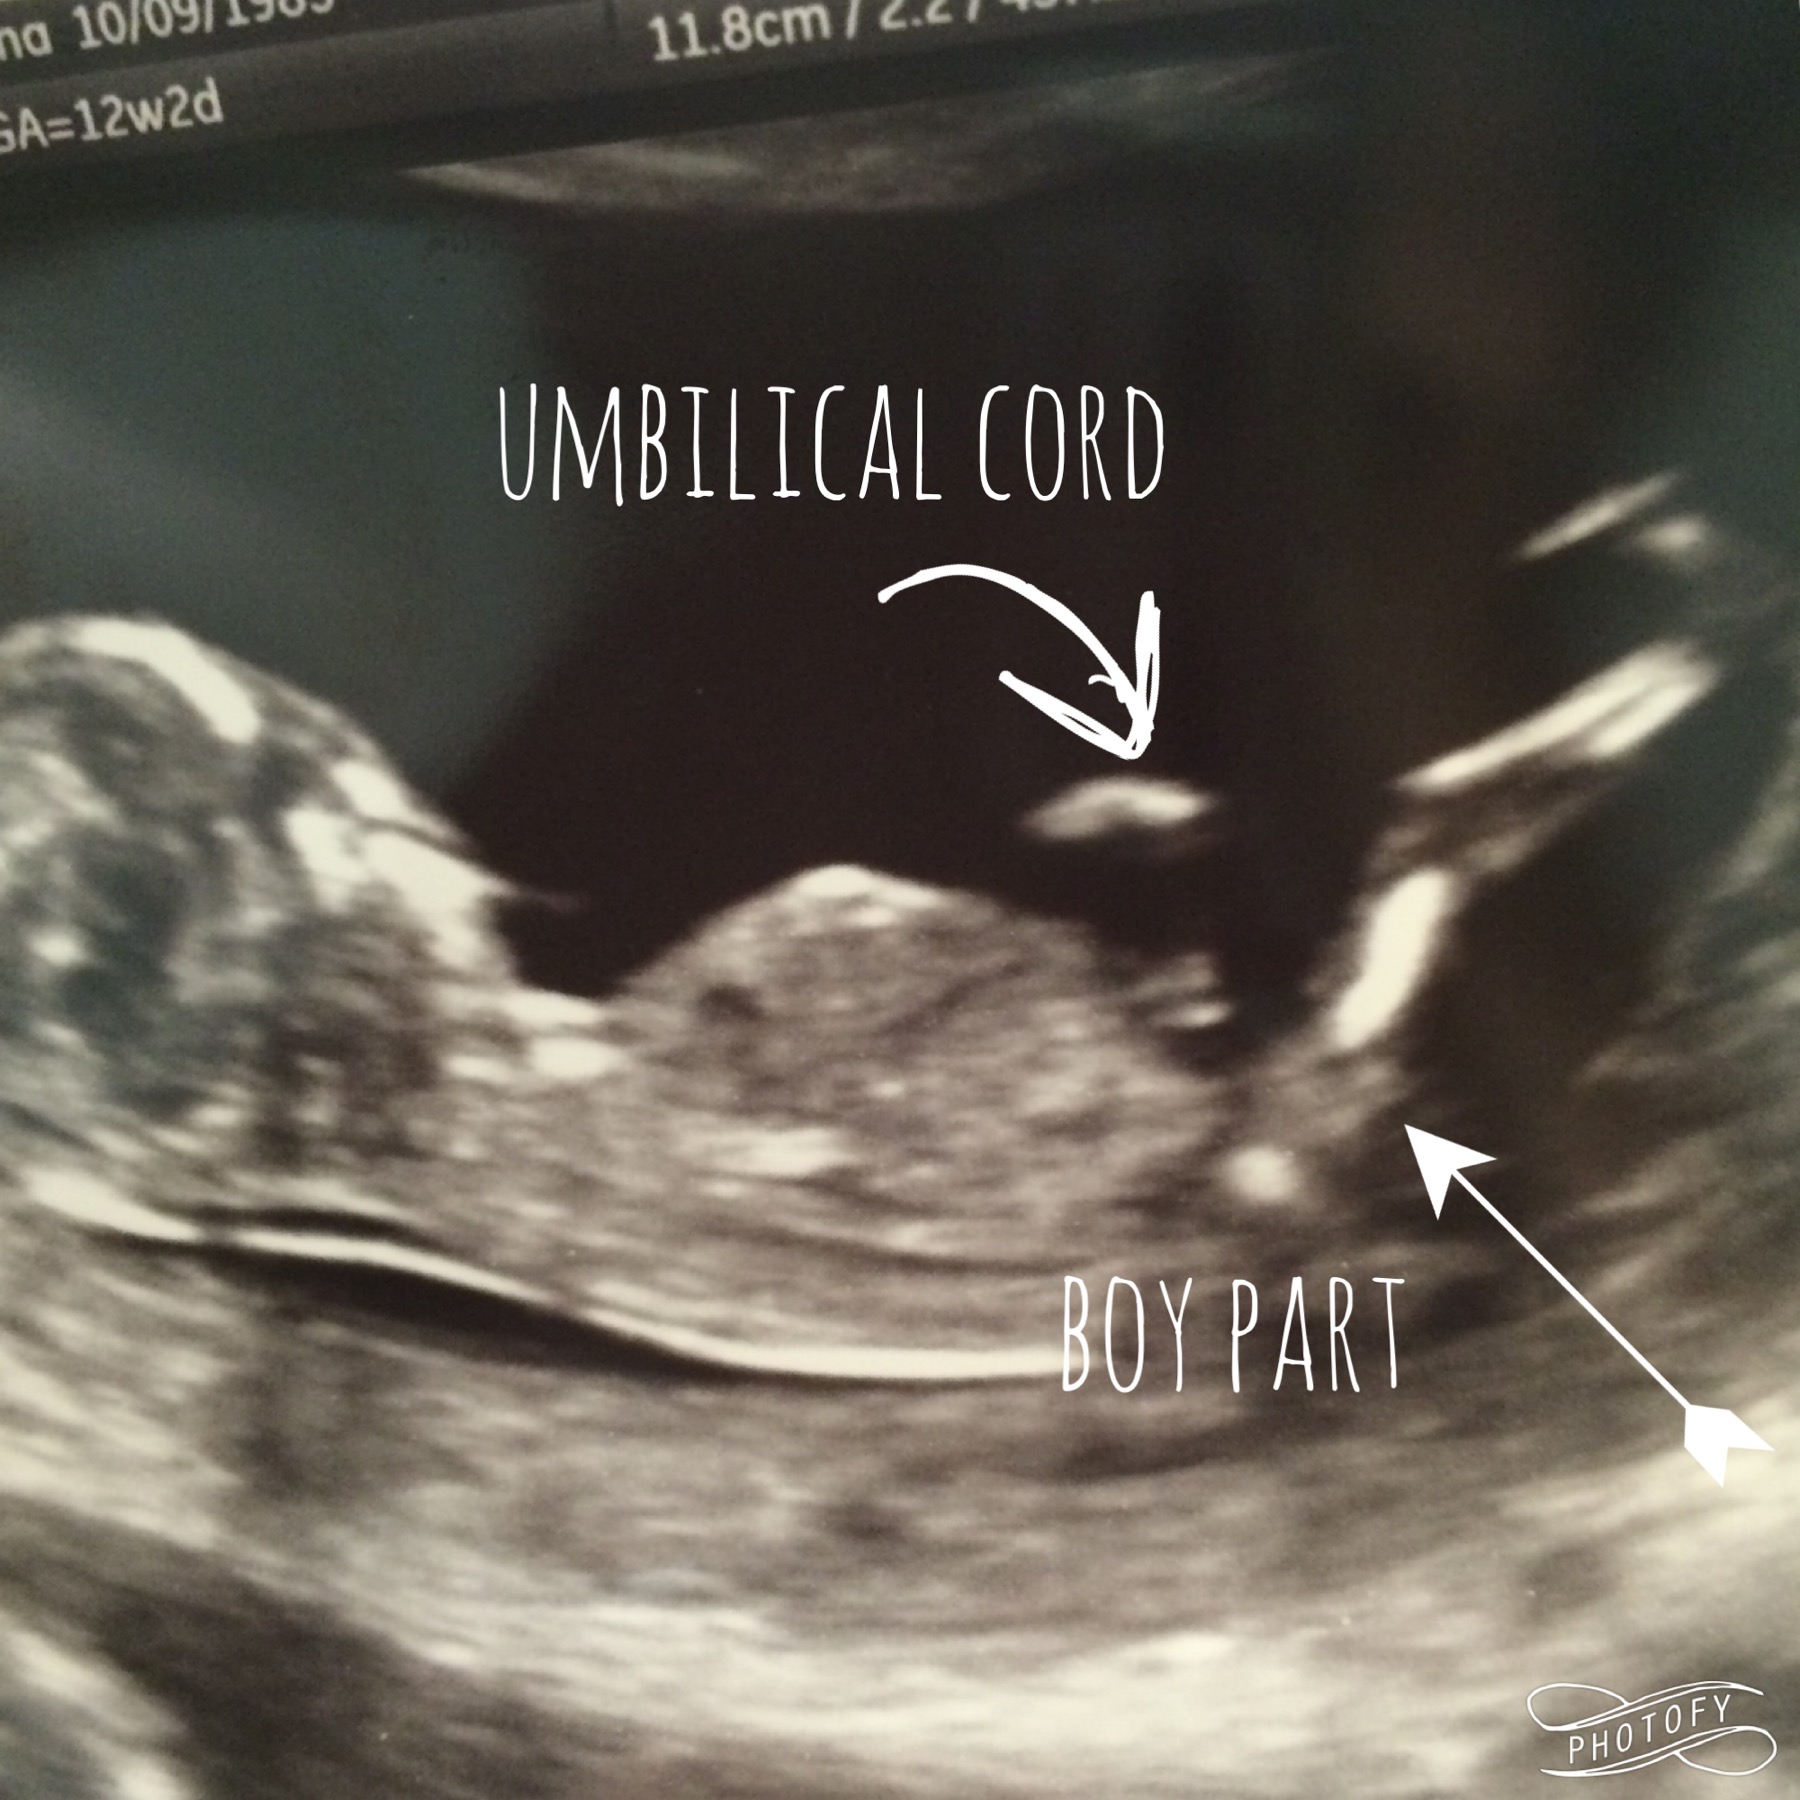

We had our NT scan today and we got some good views but I really need some input on what you think our baby is. I am 12 weeks 2 days pregnant and baby is measuring a few days larger. Thank you so much in advance for looking and guessing! ❤️

I think I would give a slight boy lean as I think I may see some stacking on that nub.

My first thought was boy.

Thabks ladies!! Our tech didn't print the really good photos she had of the nub. But we got good views of a boy part! Attachment 28513 boy I right??